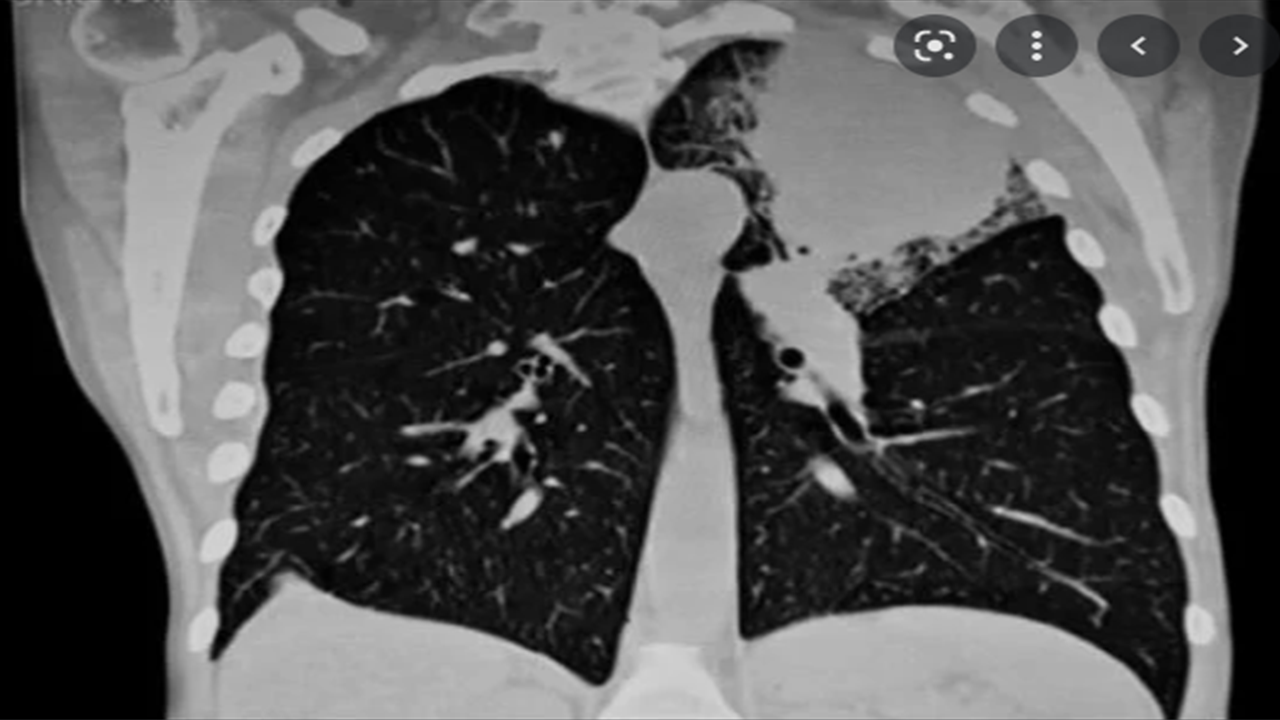

Dans ce projet de formation destiné aux résidents de chirurgie thoracique en cours de formation, nous avons utilisé la plateforme MOODLE pour la conception d’un parcours d’apprentissage dans le cadre de la prise en charge chirurgicale des cancers broncho-pulmonaires. Ce projet inclut une formation hybride associant différentes séquences d’apprentissage en mode distanciel et présentiel.

- Indiquer une chirurgie curative face à un patient présentant un cancer broncho-pulmonaire diagnostiqué.

- Gérer les différentes voies d’abord chirurgicales qui pourraient être proposées comme traitement curatif.

- Être autonomes pour la réalisation d’un abord chirurgical correct selon la présentation clinique du cancer bronchopulmonaire.

- Préparer les patients en vue d’une chirurgie curative pour cancer broncho-pulmonaire, connaitre les différents temps opératoires à réaliser pour l’exérèse, gérer les patients après le geste opératoire selon l’évolutivité et l’examen anatomopathologique définitif.